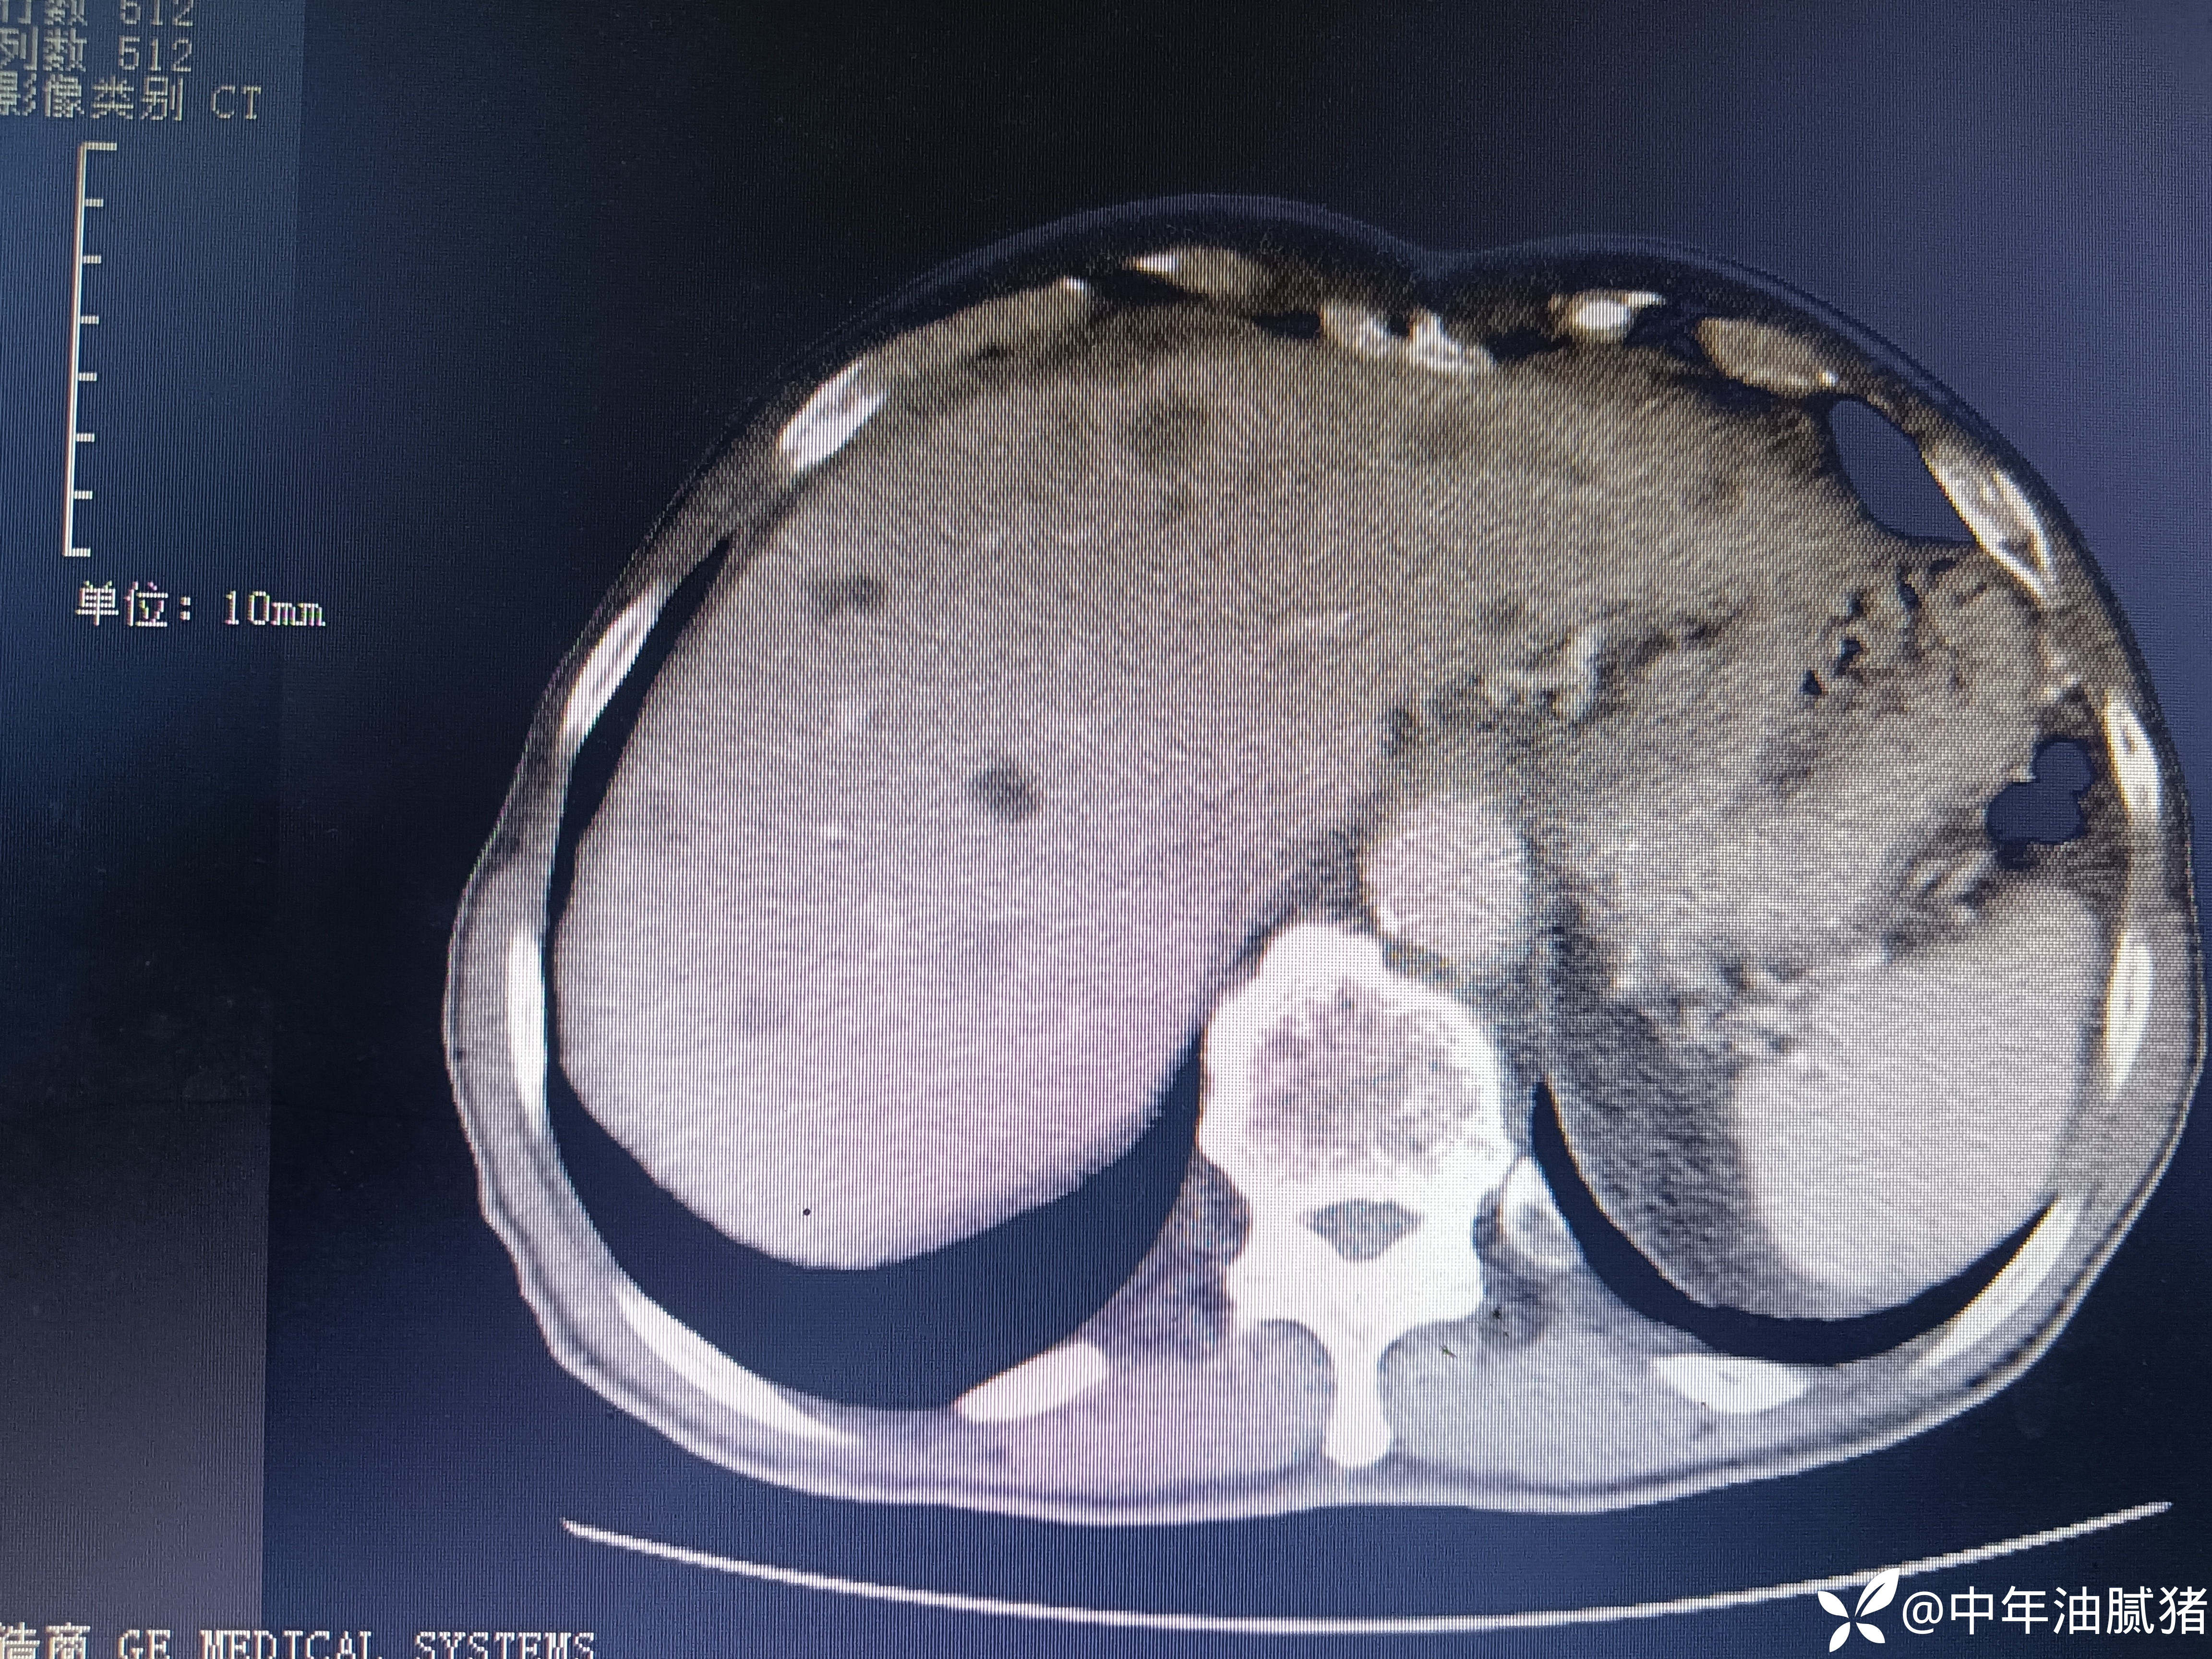

男,72岁,感胸痛7天,不剧,咳嗽时略明显,有吸烟,行肺ct报告如下

考虑肝囊肿?让他走?

我腹部ct不在行,但我记的有位大家说过:一流的先看影像再看报告,二流的先看报告再看影像,三流的只看报告!我生性浪荡,让人不安,属于二流子!上图

看后,我隐隐约约觉的不是肝囊肿那么简单?元芳,你怎么看?狄阁老,我也是这么认为!摇人,掏起手机:喂,w主任,请帮我看看这个ct。5分钟后报告修改如下